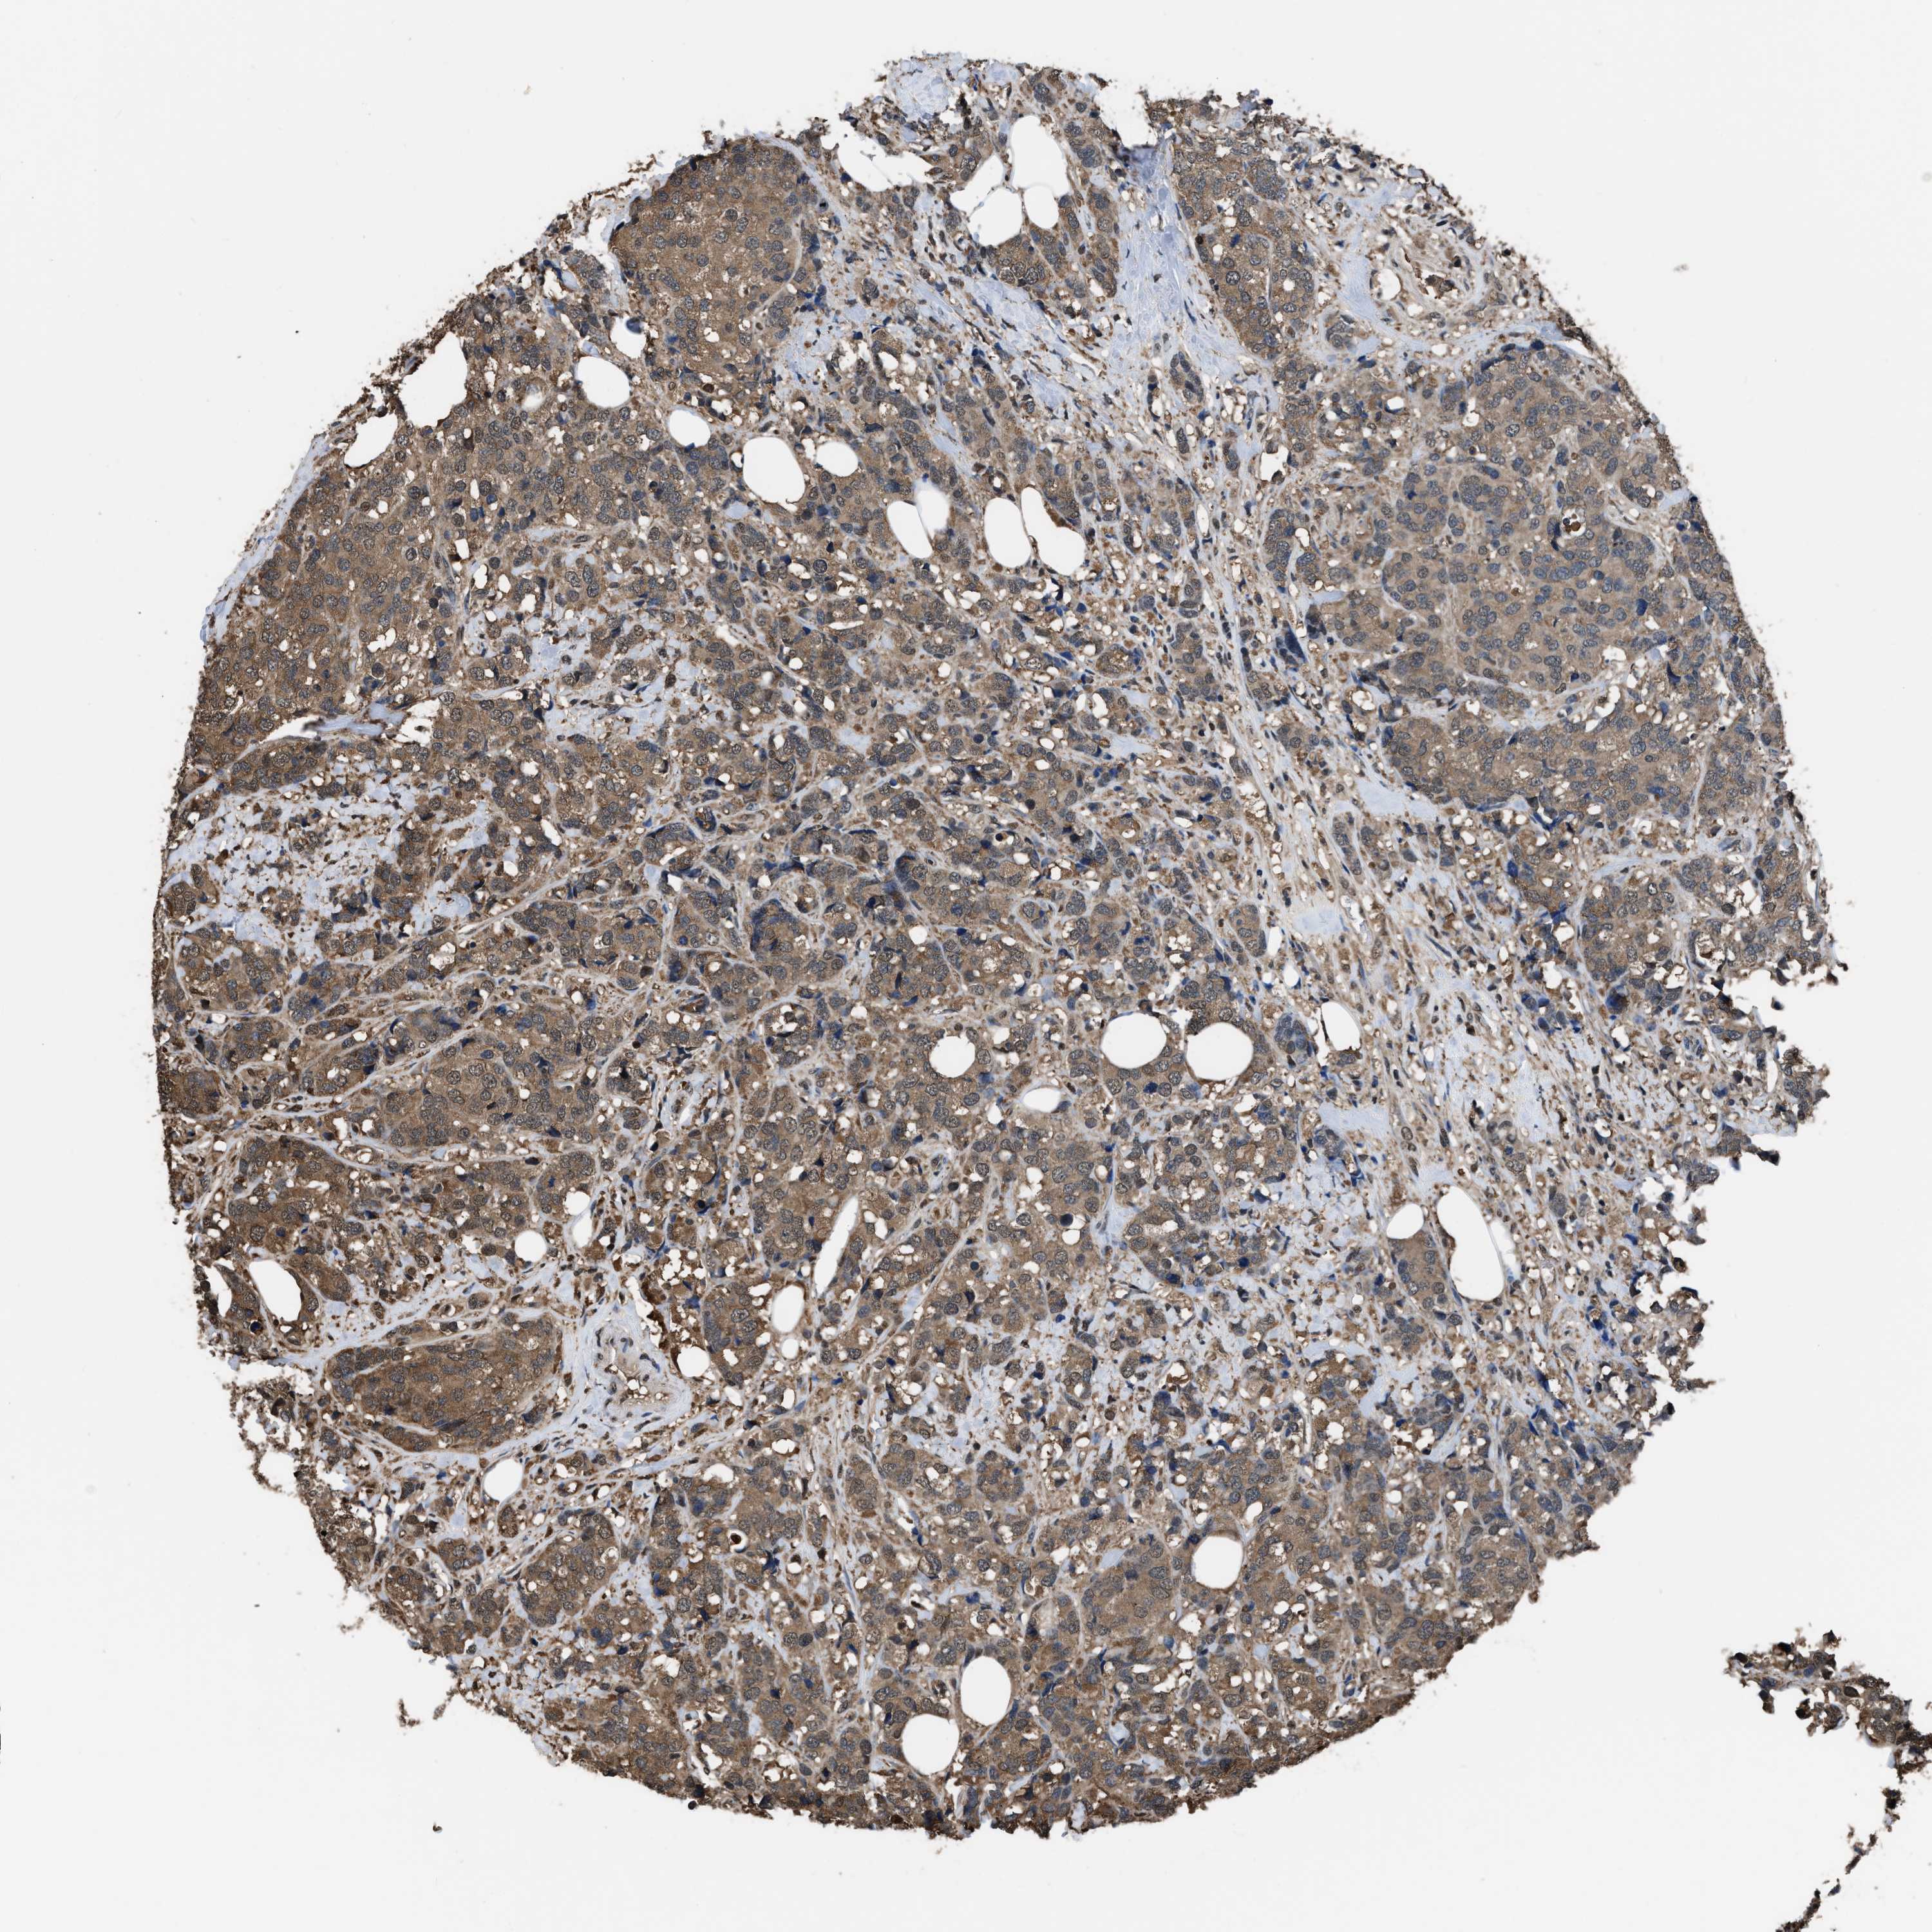

CANCER BREAST CANCER Show tissue menu

BRCA TCGA BRCA VALIDATION PROTEIN EXPRESSION